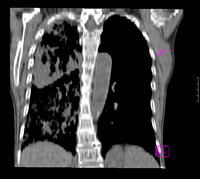

标题: CT9563:女67岁,咳嗽咯白痰伴纳差一月。右肺呼吸音低可闻及 [打印本页]

女67岁,咳嗽咯白痰伴纳差一月。右肺呼吸音低可闻及湿罗音。白细胞及淋巴细胞不高,无发烧

1、右上胸廓塌陷,纵隔气管右移

2、病灶靠后方,一般结核多见一点

3、病灶内,纵隔内有少许钙化灶

首先从简单常见入手,考虑结核,肺细支气管肺泡癌待排。

考虑结核,肺细支气管肺泡癌待排。